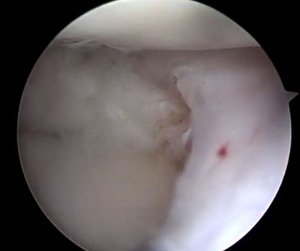

The lateral meniscal tissue appeared hypertrophied and was noted to be a Wrisberg-type discoid variant (Figure 8).

Saucerization of the redundant lateral meniscal tissue aided in the reduction of the displaced meniscus (Figure 9).